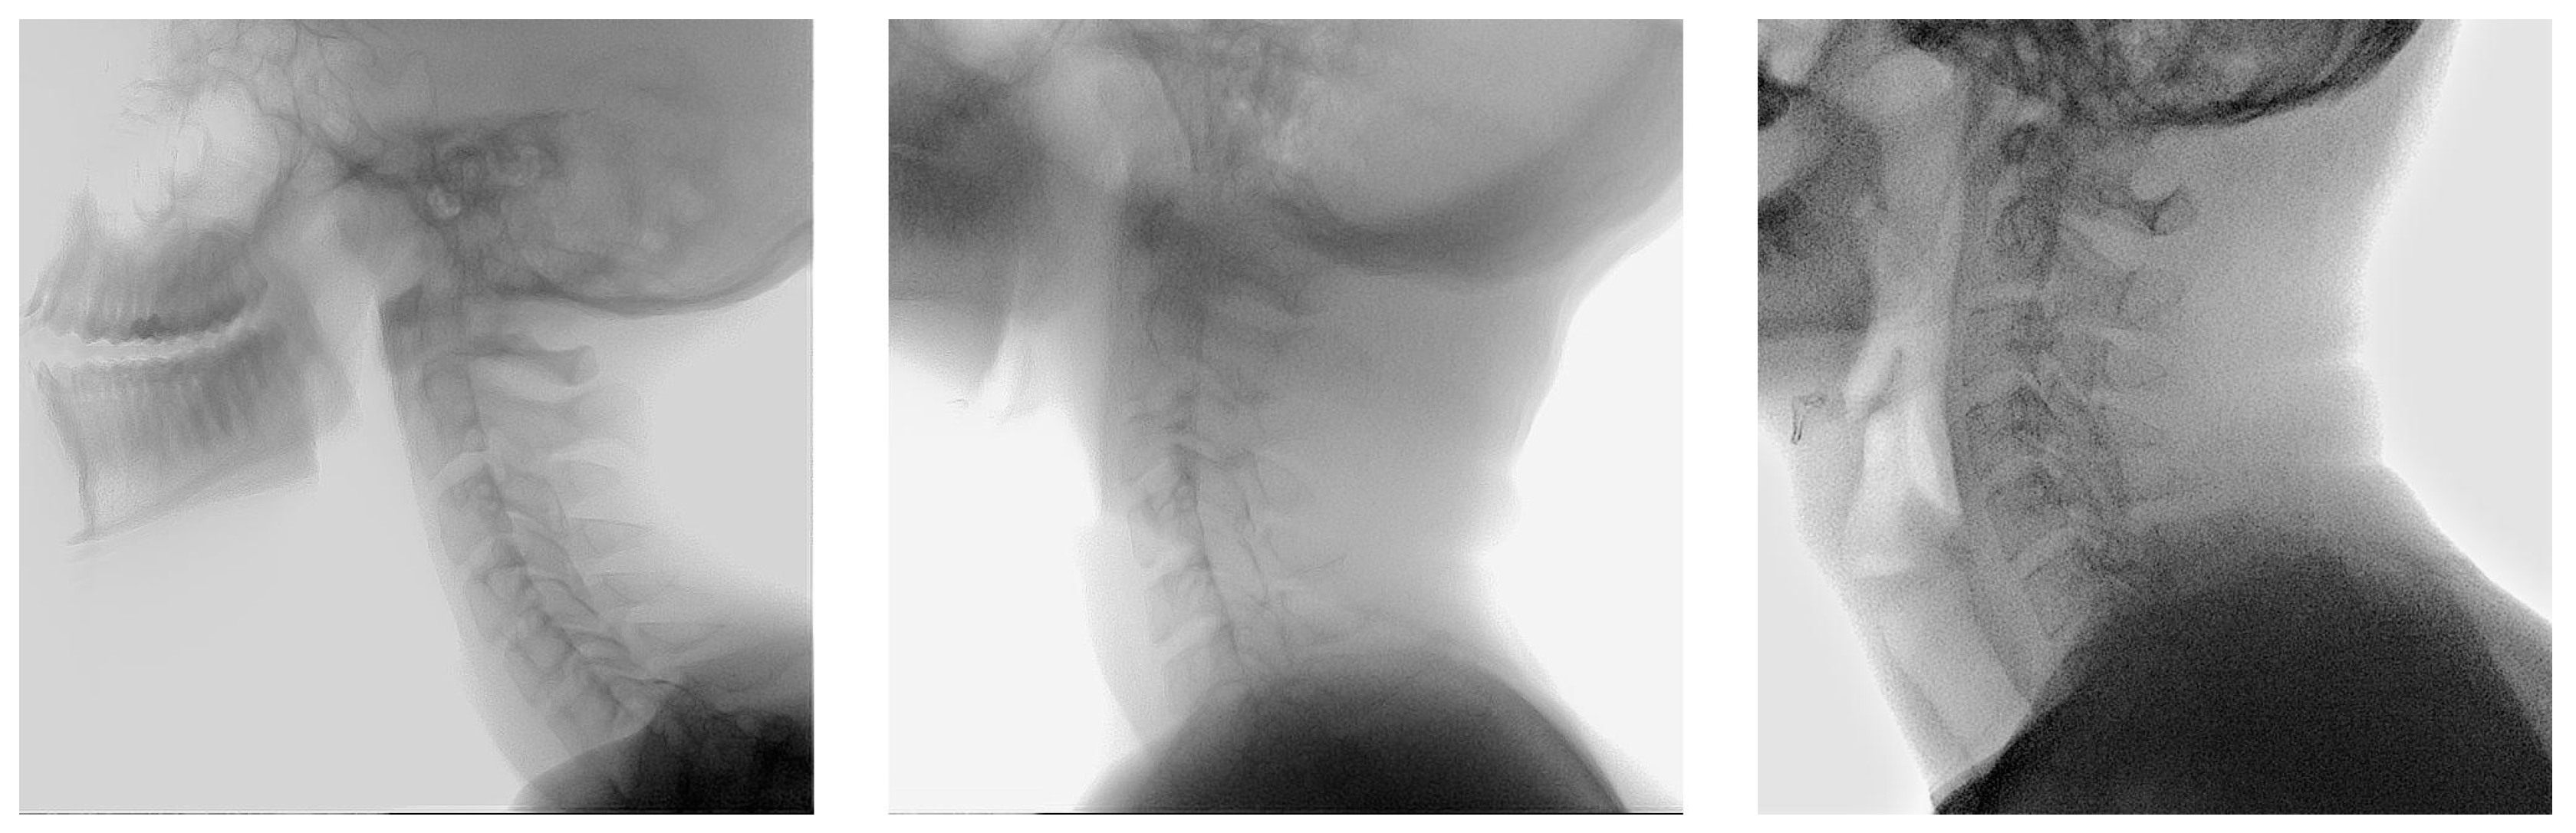

2.1. Population

2.4. Dataset